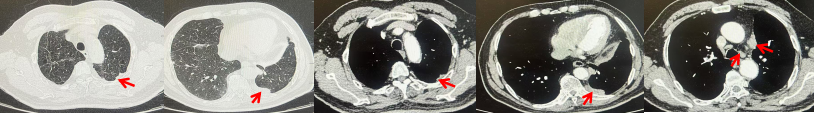

2024.09.12复查胸部CT示左侧胸膜结节,大者约为27mmx13mm,考虑转移可能性大,纵隔淋巴结增大,恶性?(如图6)。患者行胸膜穿刺活检取病理,结果示(胸膜)结合免疫组化,支持鳞状细胞癌,PD-L1(克隆号28-8)TPS约20%。分期为rT0N2bM1a IVA期,DFS为10个月。2024.09.24起行替雷利珠单抗联合紫杉醇+卡铂方案治疗4周期,复查胸CT评效SD(如图7)。后患者因脑梗塞停止治疗,于综合医院就诊,后未返院复查及治疗。

图5:患者手术前(2023.11)胸部CT肺窗及纵隔窗

图6:患者胸膜及纵隔转移(2024.09)胸部CT肺窗及纵隔窗

图7:替雷利珠单抗联合白蛋白紫杉醇+卡铂治疗4周期后(2024.12)胸部CT肺窗及纵隔窗